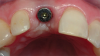

Fig 12. After implant insertion and torquing to 35 Ncm, a healing abutment was placed.

Figure 12

Different implants require the use of different drill kits for widening the osteotomy when going to depth. In the present case, the osteotomy is initially widened to 3.5 mm and taken to a depth of 11 mm (Figure 10), after which a different drill will be used to widen it to 4.3 mm and increase the depth to 13 mm to accommodate the selected implant (Figure 11).7 The implant is then inserted and properly torqued to 35 Ncm, after which a healing abutment is placed (Figure 12).